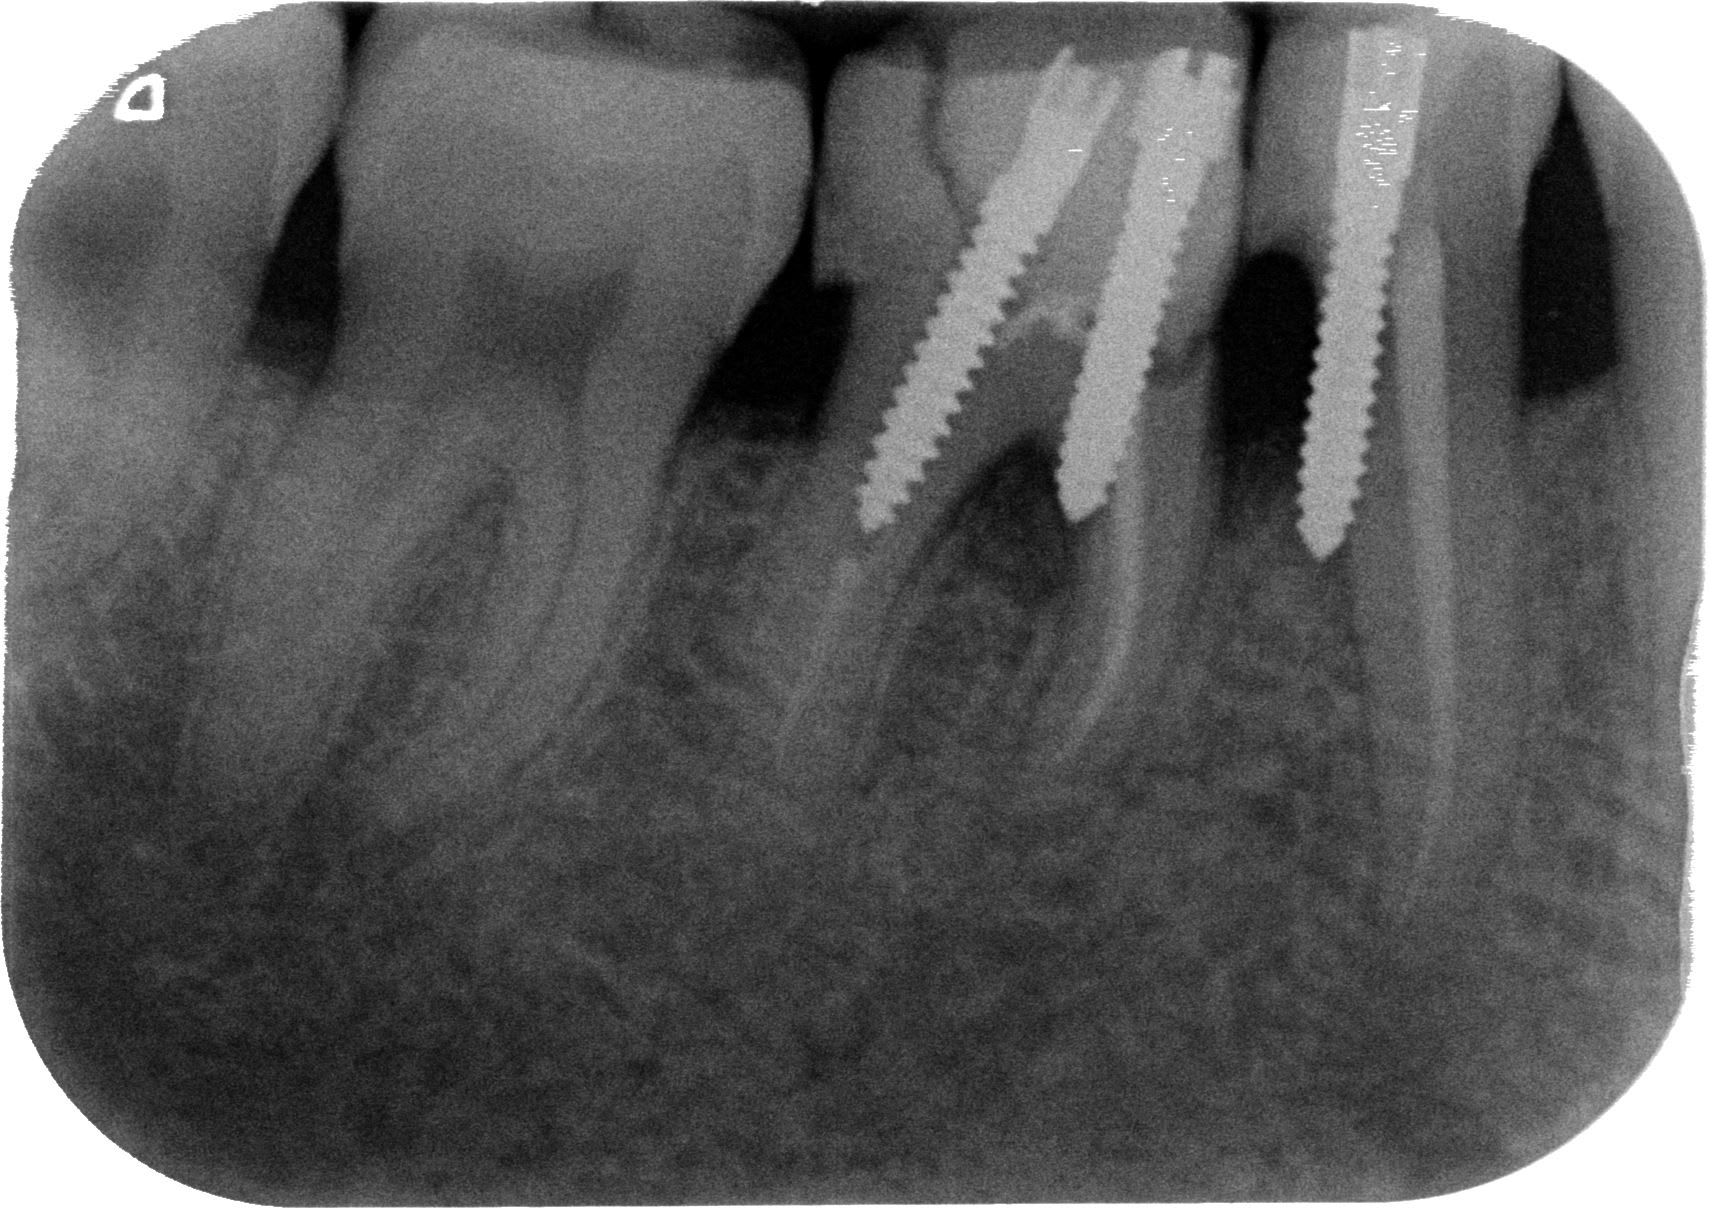

En implanto aussi, ya des pointures . Voici mon coup de coeur de la semaine :

comme pour les dds, il y a des implants inclus aussi.